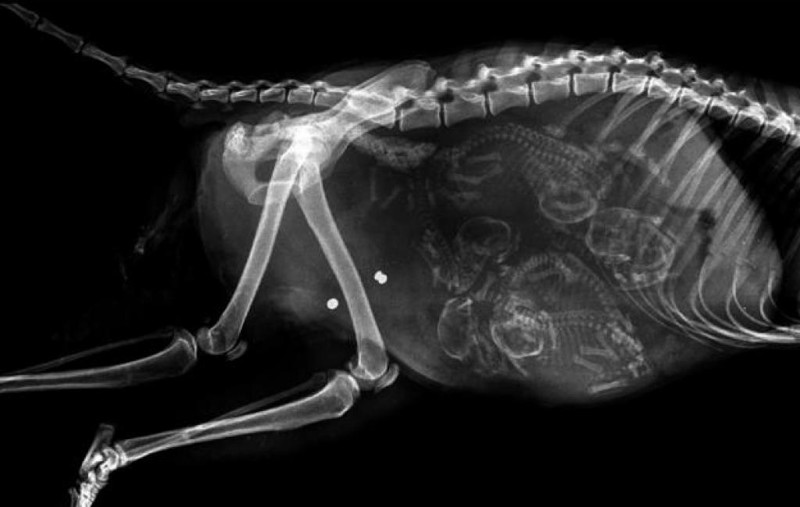

Մենք բոլորս լավ պատկերացնում ենք, թե ինչպես է անցնում մարդու հղիությունը, և շնորհիվ ժամանակակից տեխնոլոգիաների՝ կարող ենք տեսնել երեխային մայրիկի արգանդում հղիության ամենավաղ փուլում։ Իսկ ինչպե՞ս է ընթանում կենդանիների հղիությունը։ Մասնագետները, ովքեր հոգ են տանում հղի կենդանիների մասին, ներկայացրել են նրանց ռենտգենային և ուլտրաձայնային լուսանկարները, որոնք ձեր դատին է հանձնում «twizz.ru» կայքը։

Շուն